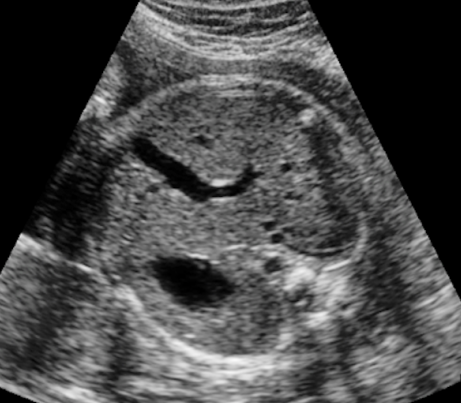

What is the feral lie based on the anatomy showed?

Breech spine down

Label the anatomy with the arrows

E. Heart (apex)

F. Lungs

G. Spine